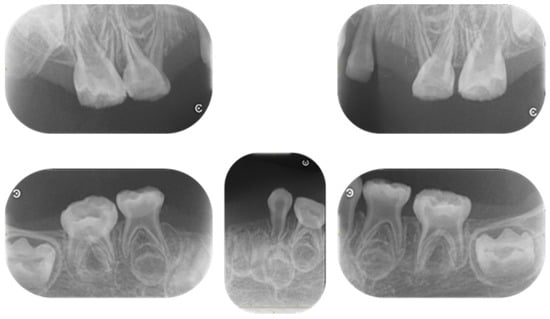

| Tooth | Time |

|---|---|

| Mandibular left primary central incisor | 1 year and 3 months |

| Mandibular right primary central incisor | 1 year and 7 months |

| Mandibular left primary lateral incisor | 2 years |

| Mandibular right primary lateral incisor | 2 years and 4 months |

| Maxillary right primary canine | 2 years and 7 months |

| Mandibular right primary canine | 2 years and 8 months |

| Maxillary right primary central incisor | 3 years |

| Maxillary left primary canine | 3 years |

| Maxillary left primary central incisor | 3 years and 9 months |

| Mandibular left primary canine | 4 years and 3 months |

| Maxillary left primary lateral incisor | 4 years and 6 months |